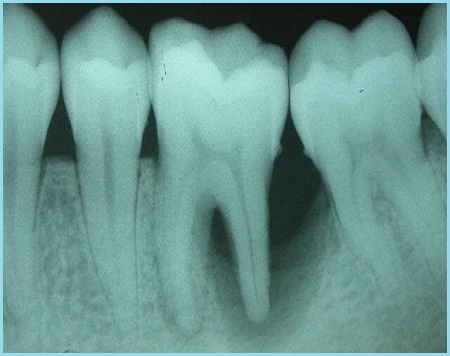

Ткань, окружающая корни зуба и удерживающая его в альвеоле, получила медицинский термин — периодонт. Соответственно, ее воспаление классифицируют как периодонтит. Локализация очага воспаления обуславливает разделение периодонтита на апикальный и маргинальный.

Причиной развития заболевания в большинстве случаев становится глубокий кариес и пульпит. При пульпите воспаление поражает мягкие ткани зуба – пульпу, затем распространяется на периодонт. Этот процесс способствует формированию кисты – своеобразного мешочка, заполненного жидкостью. В данном случае речь идет о серозном периодонтите.

Хронический периодонтит может протекать бессимптомно. Иногда наблюдается слабая боль при надкусывании больным зубом. Почти всегда такой зуб имеет измененный, сероватый оттенок; при простукивании звук получается более глухим, чем у здорового зуба. Возможно образование свища – отверстия, через которое гной из очага воспаления вытекает в ротовую полость. Свищ чаще всего выглядит как пузырёк с бело-серым содержимым в проекции верхушки больного зуба.